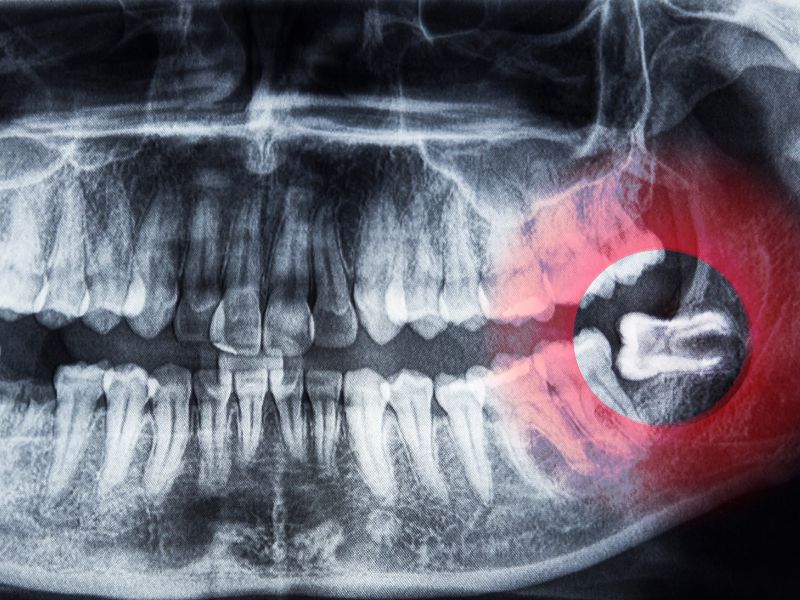

Les dents de sagesse, ou troisièmes molaires, font leur éruption en fin d’adolescence ou à l’âge adulte. Dans de nombreux cas, leur positionnement problématique peut entraîner des douleurs, infections ou désalignements dentaires. Le Dr Silviu Oratie évalue la nécessité de leur extraction au cas par cas, dans un cadre sécurisé.

- Inclusion partielle ou totale dans la gencive ou l’os

- Manque de place sur l’arcade dentaire

Après un bilan clinique et radiographique (panoramique ou cone beam 3D), l’indication est posée. L’intervention se fait :